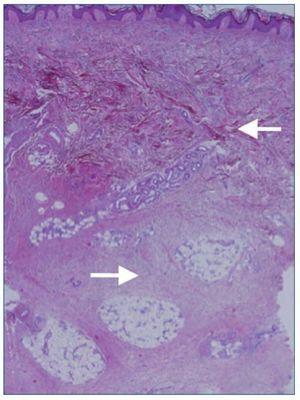

Por último, se realizaron dos biopsias cutáneas en las que se objetivó una fibrosis dérmica difusa que se extendía al panículo adiposo (figura 1). Se observaban fibroblastos entre los haces de colágeno. Dichos fibroblastos fueron positivos mediante inmunohistoquímica para el CD34. Los hallazgos histológicos fueron sugestivos de fibrosis nefrogénica4.

Figura 1. Biopsia cutánea. Fibrosis dérmica difusa (R). Paniculitis septal crónica (r).